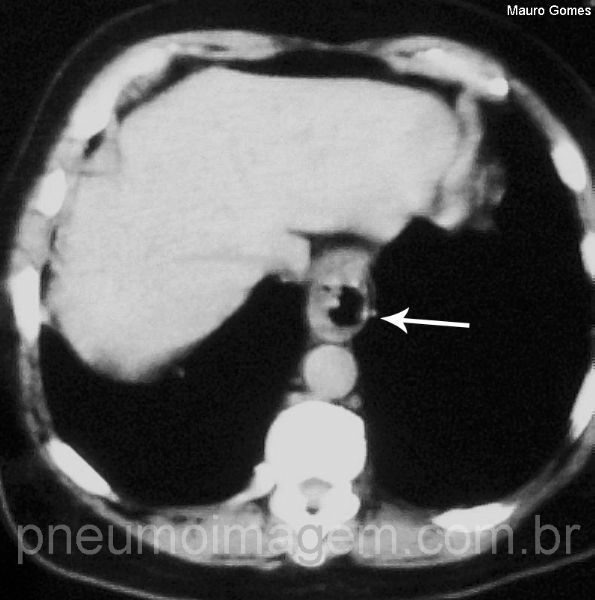

Neste corte tomográfico pode-se observar a hérnia hiatal (seta branca).

Chaves: hiatus hernia (white arrow), sliding hiatus hernia (white arrow); hiatal hernia.